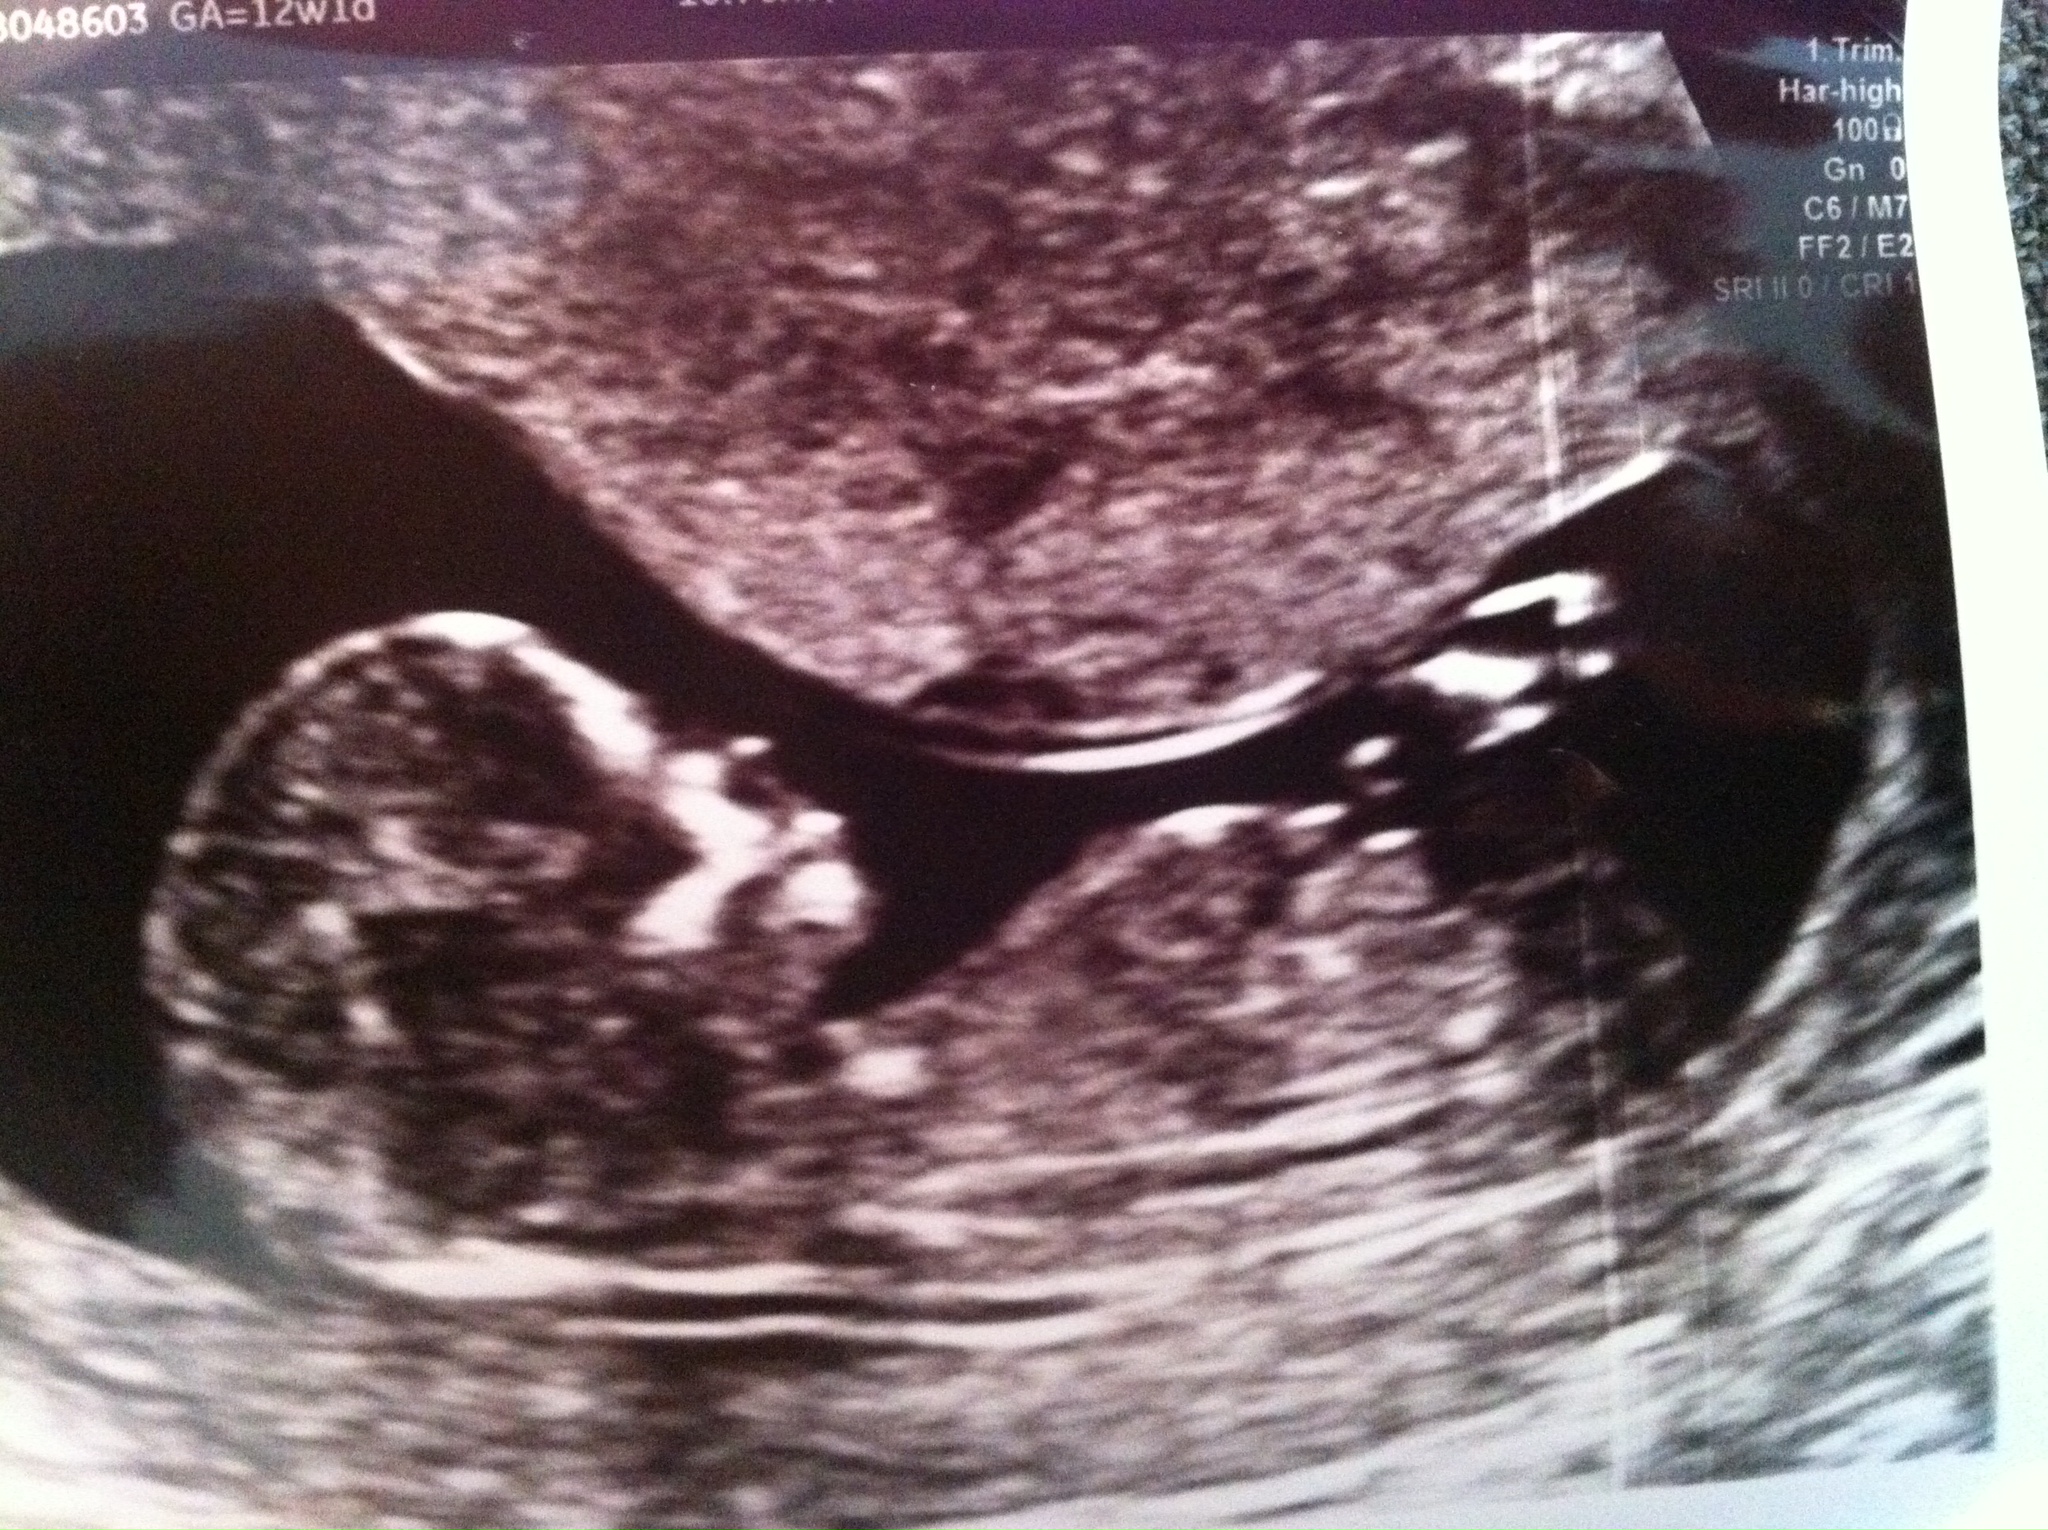

Nub at 13 weeks:

Attachment 20055